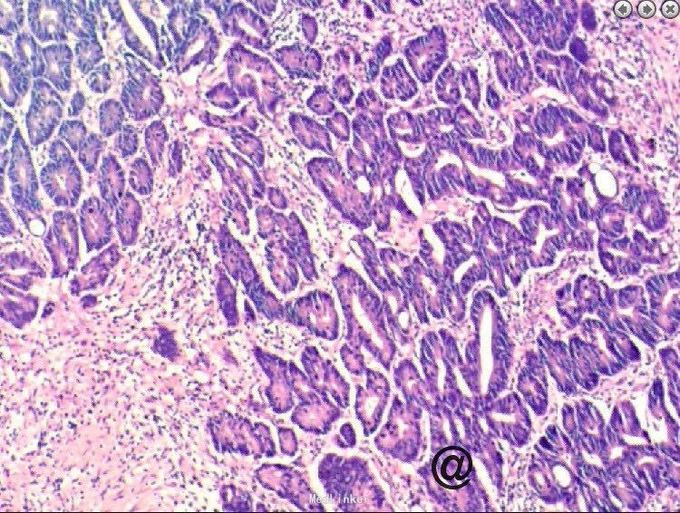

请妇科会诊,该科医师行妇检未见明显包块,且CA125正常,建议行小肠检查,同时行彩超探查了解包块来源,妇科彩超:子宫较小,宫体后壁肌壁间肌瘤(稍凸向宫腔),右侧附件区实质性包块,考虑为右侧卵巢肿瘤,左侧附件区未见明显异常显示,盆腔未见明显积液。 请妇科商议并于患者沟通后于2015.10.08转入妇科,转科行积极完善术前准备,于10.16行剖腹探查术。术中见:子宫稍大,质硬,后壁与直肠致密粘连,左侧卵巢大小正常,右侧卵巢增大直径约4cm,双侧附件与子宫后壁及盆壁致密粘连,分离盆腔粘连后可见巧克力样液体,阑尾可见约9*5*4cm肿瘤,包膜完整,与周围组织无粘连。请胃肠外科主任上台会诊,行阑尾切除术,术中快速病理切片检查示:(阑尾)腺上皮高级别上皮内瘤变(腺上皮中-重度异型增生),确诊待常规。再次向家属交代病情,将快切结果告知患者家属,患者家属了解病情,要求切除右半结肠,切除全子宫及双侧附件,最终行:全麻插管下行右半结肠根治性切除+肠粘连松解+腹式全子宫切除+双侧卵巢输卵管切除术。术后病检提示:(阑尾)中分化腺癌,癌浸润达肌层。阑尾手术切缘未见癌组织。免疫组化:CK19(+),Ki-67 LI约60%。子宫附件及右半结肠:1.送检肠管粘膜组织呈慢性炎,粘膜下水肿,纤维脂肪组织增生,血管扩张、充血。肠周触及淋巴结13枚呈反应性增生。 2.子宫腺肌症,囊性萎缩性子宫内膜组织,慢性子宫颈炎伴鳞状上皮化生。 3.(双侧)卵巢白体形成,(右侧)符合子宫内膜异位囊肿;(双侧)输卵管组织呈慢性炎,(右侧)伴系膜囊肿。